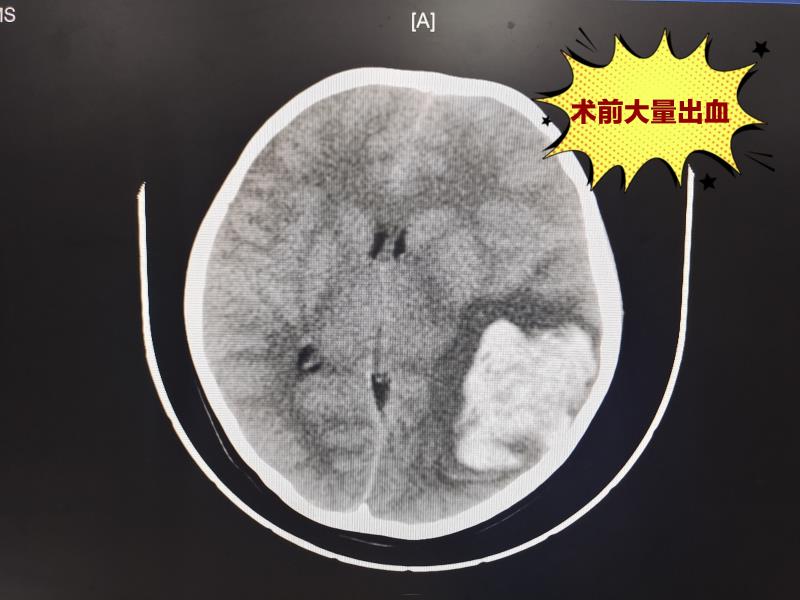

刻不容缓!抢救脑出血女童的生死时速

近日,安化县人民医院神经外科为一名年仅10岁的脑动脉畸形破裂伴蛛网膜下腔出血患者成功实施手术!获得了患者和家属的一致好评!

患者王某,是一名10岁女童,家属代述患者无明显诱因下突发昏迷,呼唤无言语应答,刺激肢体无反应,伴恶心呕吐,家属急送我院就诊,急诊医师完善相关辅助检查后,以“脑出血”收至我科。神经外科主任谌育斌和主管医生戴胜了解到情况后,立即评估患者,取得家属同意,在最短时间内进行手术。

术后患者神志清楚,原出血灶较前明显减少,恢复良好,步态自如,于近日顺利出院。